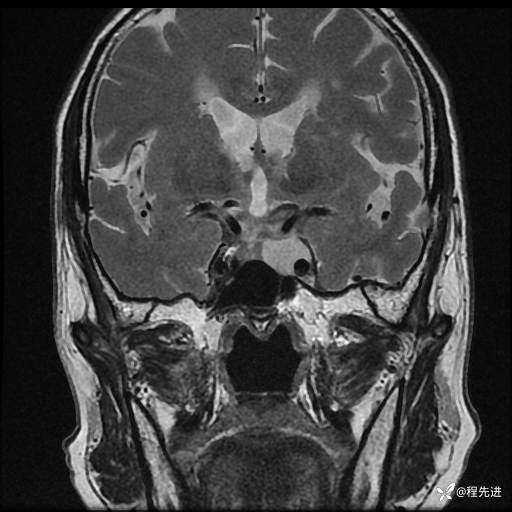

MRI平扫+增强:

T2: